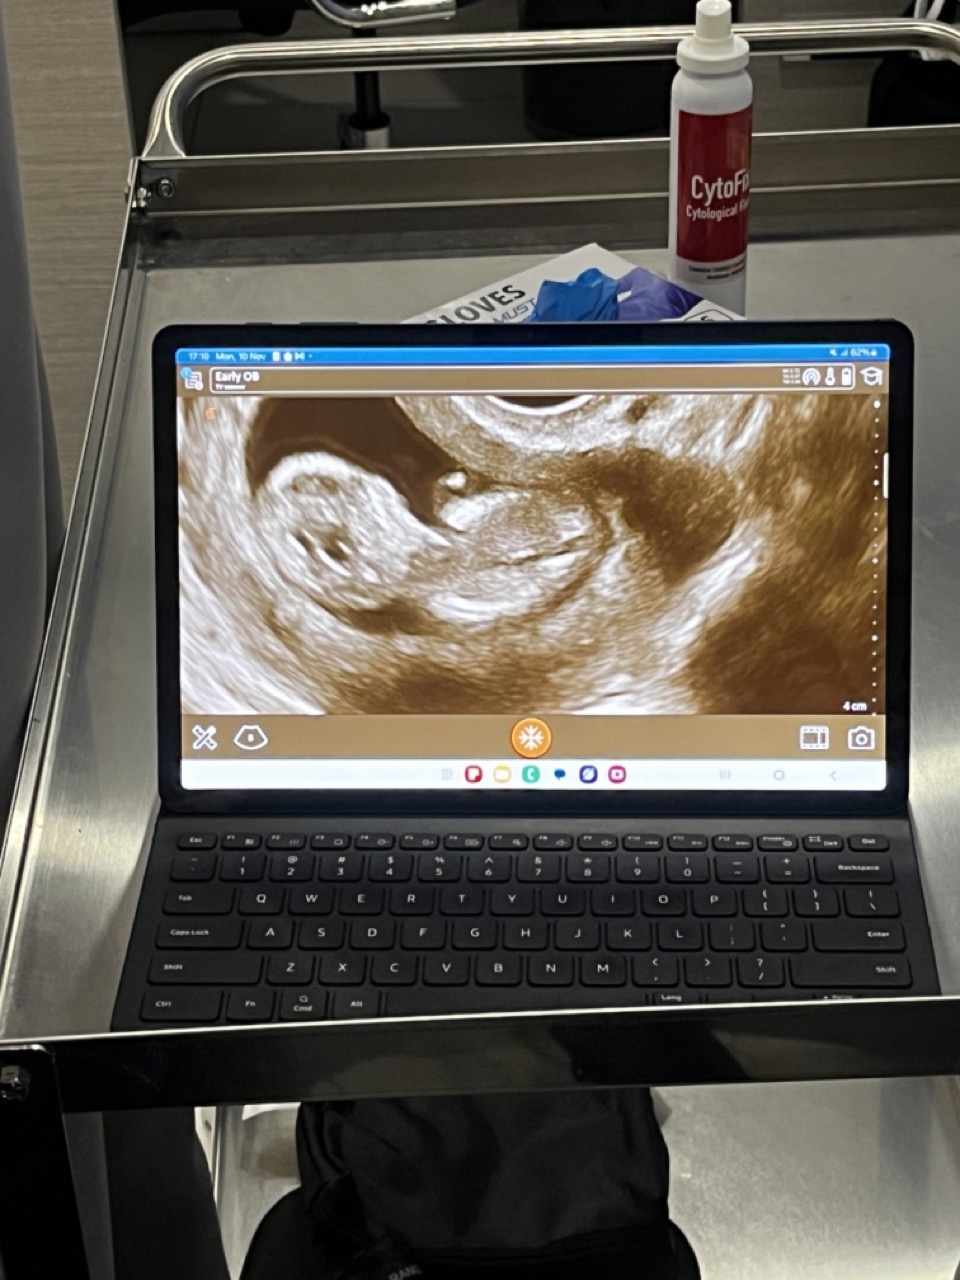

Yesterday we got to see our baby again (3rd time so far) on an ultrasound.

11 weeks, 4 days, and due in May 2026.

Tiny arms, legs, and head. Already moving around.

Either way, everything looked good.

Heartbeat strong. Growth on track.

Wild to think there’s a whole person forming in there.